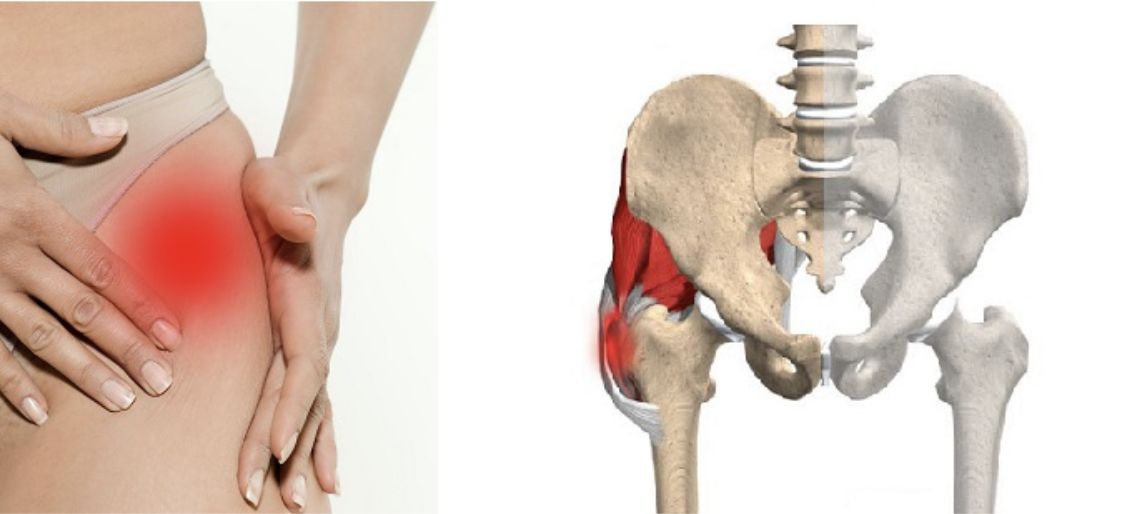

Здоровье суставов: Трохантерит и его влияние на мышцы